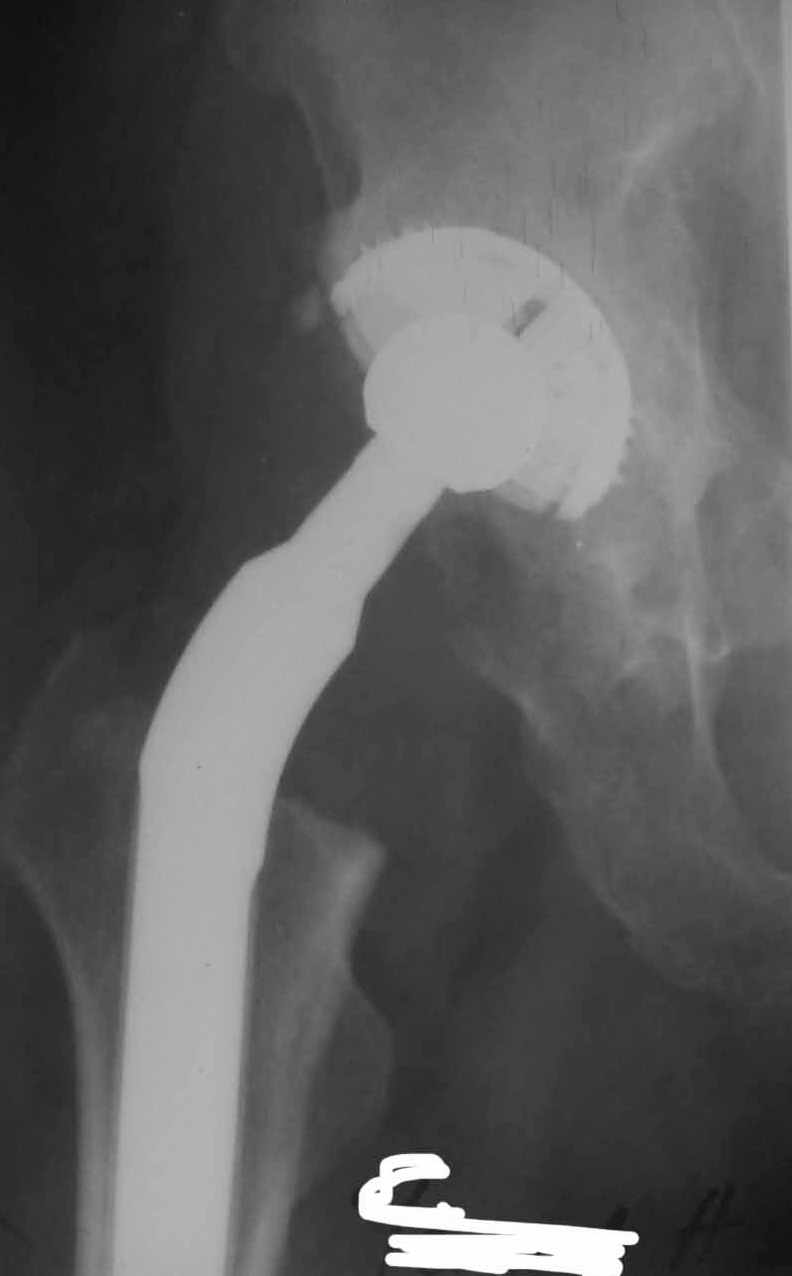

Во вложении - рентгенограммы после вывиха и после вправления.

Идея очень простая, в случае, если удасться прожить без вывиха 2.5-3 месяца, вероятность его возникновения в будущем значительно уменьшится. Оптимальный вариант - повторная иммобилизация на срок 6 недель с нагрузкой на ногу (как бы я ни не любил гипс, но этот путь проверенный и может дать результат). Если это невозможно, то исключительно осторожная реабилитация под строгим контролем без резких движений (спать в положении на спине с отведением и подушкой под коленкой и т.д.). Ходьба сама по себе не опасна, опасен переход от положения "лежа" в положение "полусидя" и "стоя" и наоборот.

1. AP X ray of the Pelvis is a must. It will likely show that right hip/ femur is longer than left. Even based on Rt Hip AP X Ray it is my impression.

2. 2. Acetabular component is not vertical but rather anteverted, and also small ( small size was likely used because of the deficient posterior wall of the acetabulum).

3. Femoral component is malaligned relatively to the acetabular and combination of this factors (head is also small for this patient) is the reason for dislocation.( was likely anterior)